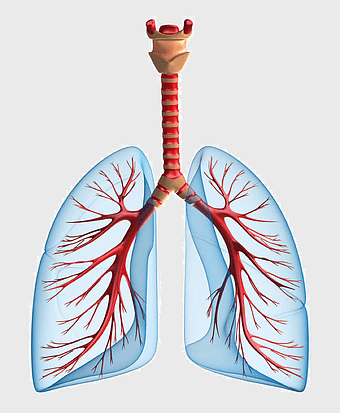

Pulmonary pleurae, Lung Tuberculosis, Pleural cavity, respiratory system, lung anatomy, medical illustration, pulmonary health, PNG

- Pulmonary pleurae

- Lung Tuberculosis

- Pleural cavity

- respiratory system

- lung anatomy

- medical illustration

- pulmonary health